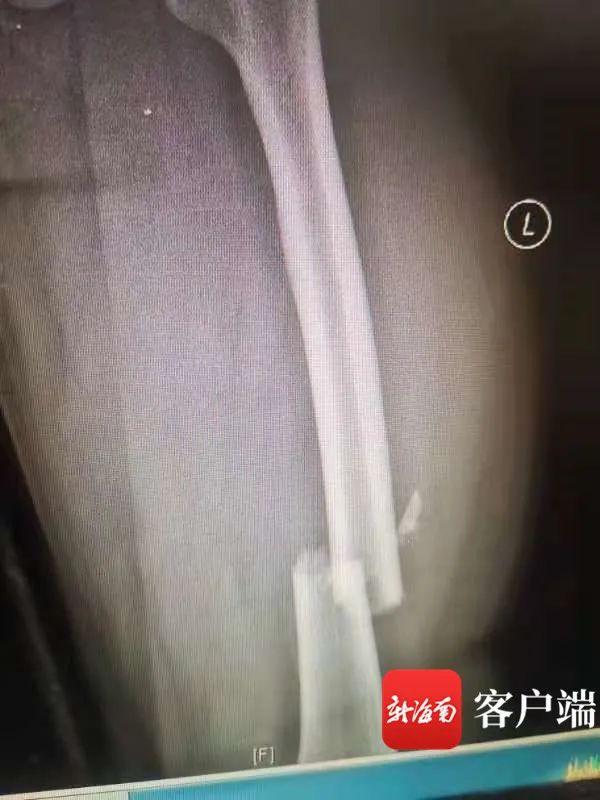

目前,王某和琼A5**51黑色小轿车的司机刘某均有不同程度的受伤,警方经对王某进行抽血检测,结果显示其血液中的酒精含量为152mg/100ml,属于醉酒驾驶。王某腰椎多处骨折受伤,刘某股骨骨折,没有生命危险正在医院进一步观察治疗。